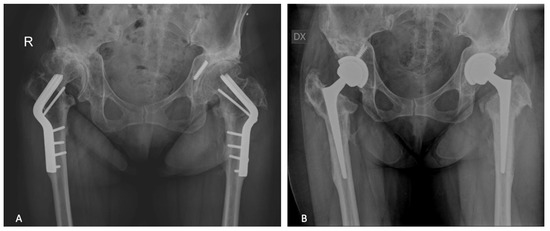

| Post-Traumatic Group | Post-Preventive Group | |

| Number of hips | 87 | 40 |

| Index surgery | ||

| Subtrochanteric fracture | 34 (39%) | - |

| Pertrochanteric fracture | 45 (51%) | - |

| Shaft fracture | 7 (8%) | - |

| Acetabular fracture | 1 (1%) | - |

| Hip dysplasia | - | 23 (57%) |

| Epiphysiolysis | - | 14 (35%) |

| Osteonecrosis | - | 1 (2%) |

| Arthrodesis | - | 2 (5%) |

| Hardware removed | ||

| Intramedullary nail | 31 (24%) | - |

| Küntscher nail | 1 (1%) | - |

| Dynamic hip screw | 14 (11%) | - |

| Screws | 35 (27%) | 13 (10%) |

| plate and screws | 6 (5%) | 9 (7%) |

| Angled blade plate | - | 12 (10%) |

| Tantalum rod | - | 1 (1%) |

| K wires | - | 1 (1%) |

| Camber | - | 4 (3%) |

| Type of femoral stem used for conversion THA | ||

| Cementless | ||

| Conventional tapered | 31 (24%) | 7 (6%) |

| Short tapered | 16 (13%) | 8 (6%) |

| Conical | 4 (3%) | 21 (17%) |

| Long revision | 31 (24%) | 4 (3%) |

| Resurfacing | 1 (1%) | - |

| Cemented | ||

| Conventional tapered | 4 (3%) | - |